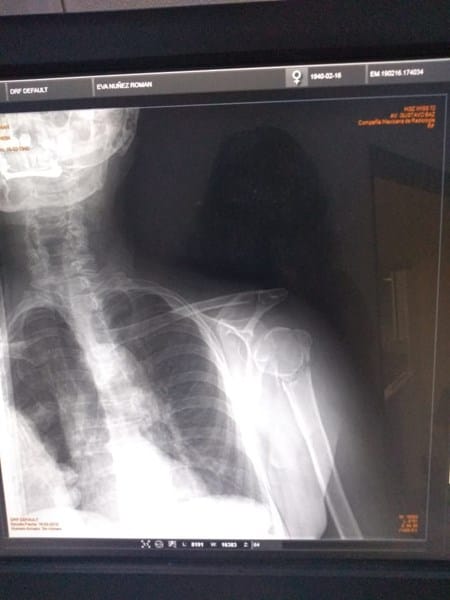

¿Rayos x, el humero está roto?

El hueso humero del brazo derecho está safado (dislocado), pero quisiera saber si la diafisis está rota, justo abajo de la epífisis.

Fue a causa de una caída, en caso de las radiografías, quisiera saber como es que se debería proceder con la "sanación, cirugía, curación"